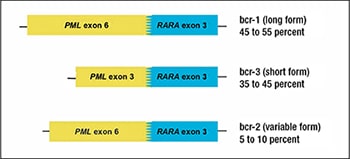

The PML gene, or promyelocytic leukemia gene, is located on chromosome 15.2 Its gene product is a tumor suppressor protein that blocks cell proliferation and regulates apoptosis via FAS ligand and tumor necrosis factor-alpha. The RARA gene, or retinoic acid receptor-alpha, is located on chromosome 17.3 The RARA gene codes for a nuclear receptor that regulates gene transcription, including genes involved in differentiation, apoptosis, and granulopoiesis. The translocation between PML and RARA occurs between the long arms of both chromosomes 15 and 17, respectively. The breakpoint of RARA occurs at intron 2, but the breakpoint of PML can occur at three different locations, resulting in different transcript sizes with similar functions (Fig. 1).4

The most common breakpoint subtype of PML, bcr-1 (breakpoint cluster region) or long form, is at intron 6, which occurs in 45 to 55 percent of APL cases.4 The second most common is the short form, or bcr-3, which occurs in 35 to 45 percent of cases and occurs at intron 3 of PML. Finally, the least common subtype is the variable form, or bcr-2, which occurs in five to 10 percent of cases and occurs at exon 6 of PML. The bcr-2 form is termed variable form because the breakpoints can occur at different sites within exon 6. The resulting PML-RARA fusion gene product prevents normal transcription, which ultimately leads to lack of differentiation of myeloid cells and provides cells with a survival advantage.